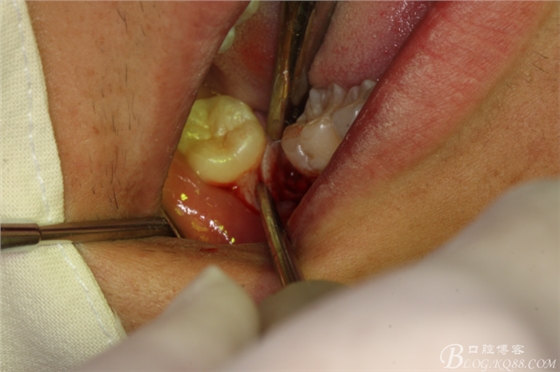

圖10.橫斷牙冠的影像

圖11.牙挺分開(kāi)47牙冠

圖12.挺出47頰側(cè)牙冠